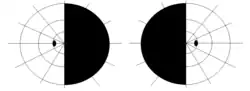

| |

| Visual pathway lesions From top to bottom: 1. Complete loss of vision in the right eye 2. Bitemporal hemianopia 3. Homonymous hemianopia 4. Quadrantanopia 5.& 6. Quadrantanopia with macular sparing | |

The type of field defect can help localize where the lesion is located (see picture given in infobox).